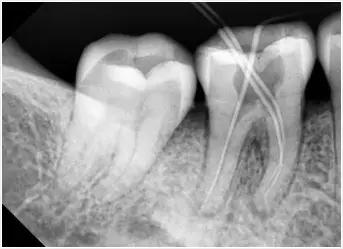

確定根管長度